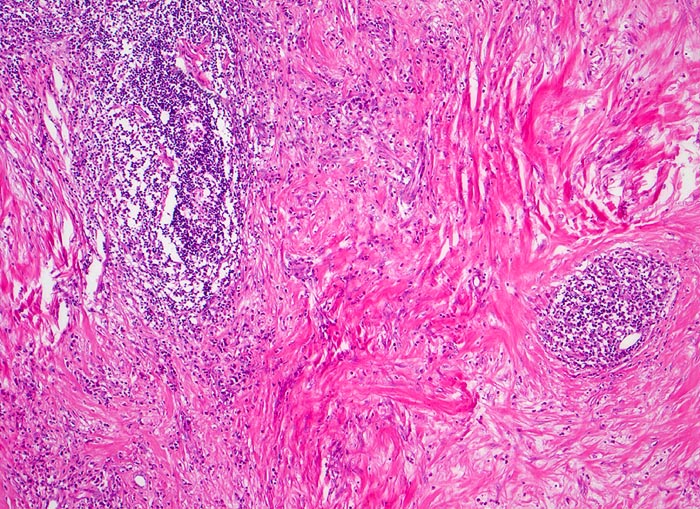

Histologisch charakteristisch für diesen Subtyp sind Sklerose, noduläres Wachstumsmuster und Lakunarzellen. Bei der nodulären Sklerose können Grad I und Grad II (15-25%) Lymphome unterschieden werden; unter modernen Therapiekonzepten allerdings ohne prognostische Bedeutung

• Zerstörung der Lymphknotenarchitektur.

• Von breiten Bindegewebssträngen abgegrenzte Knoten.

• Die Knoten bestehen vorwiegend aus einem Mischzellinfiltrat reaktiver Zellen: Lymphozyten, Histiozyten, eosinophile Granulozyten und Plasmazellen.